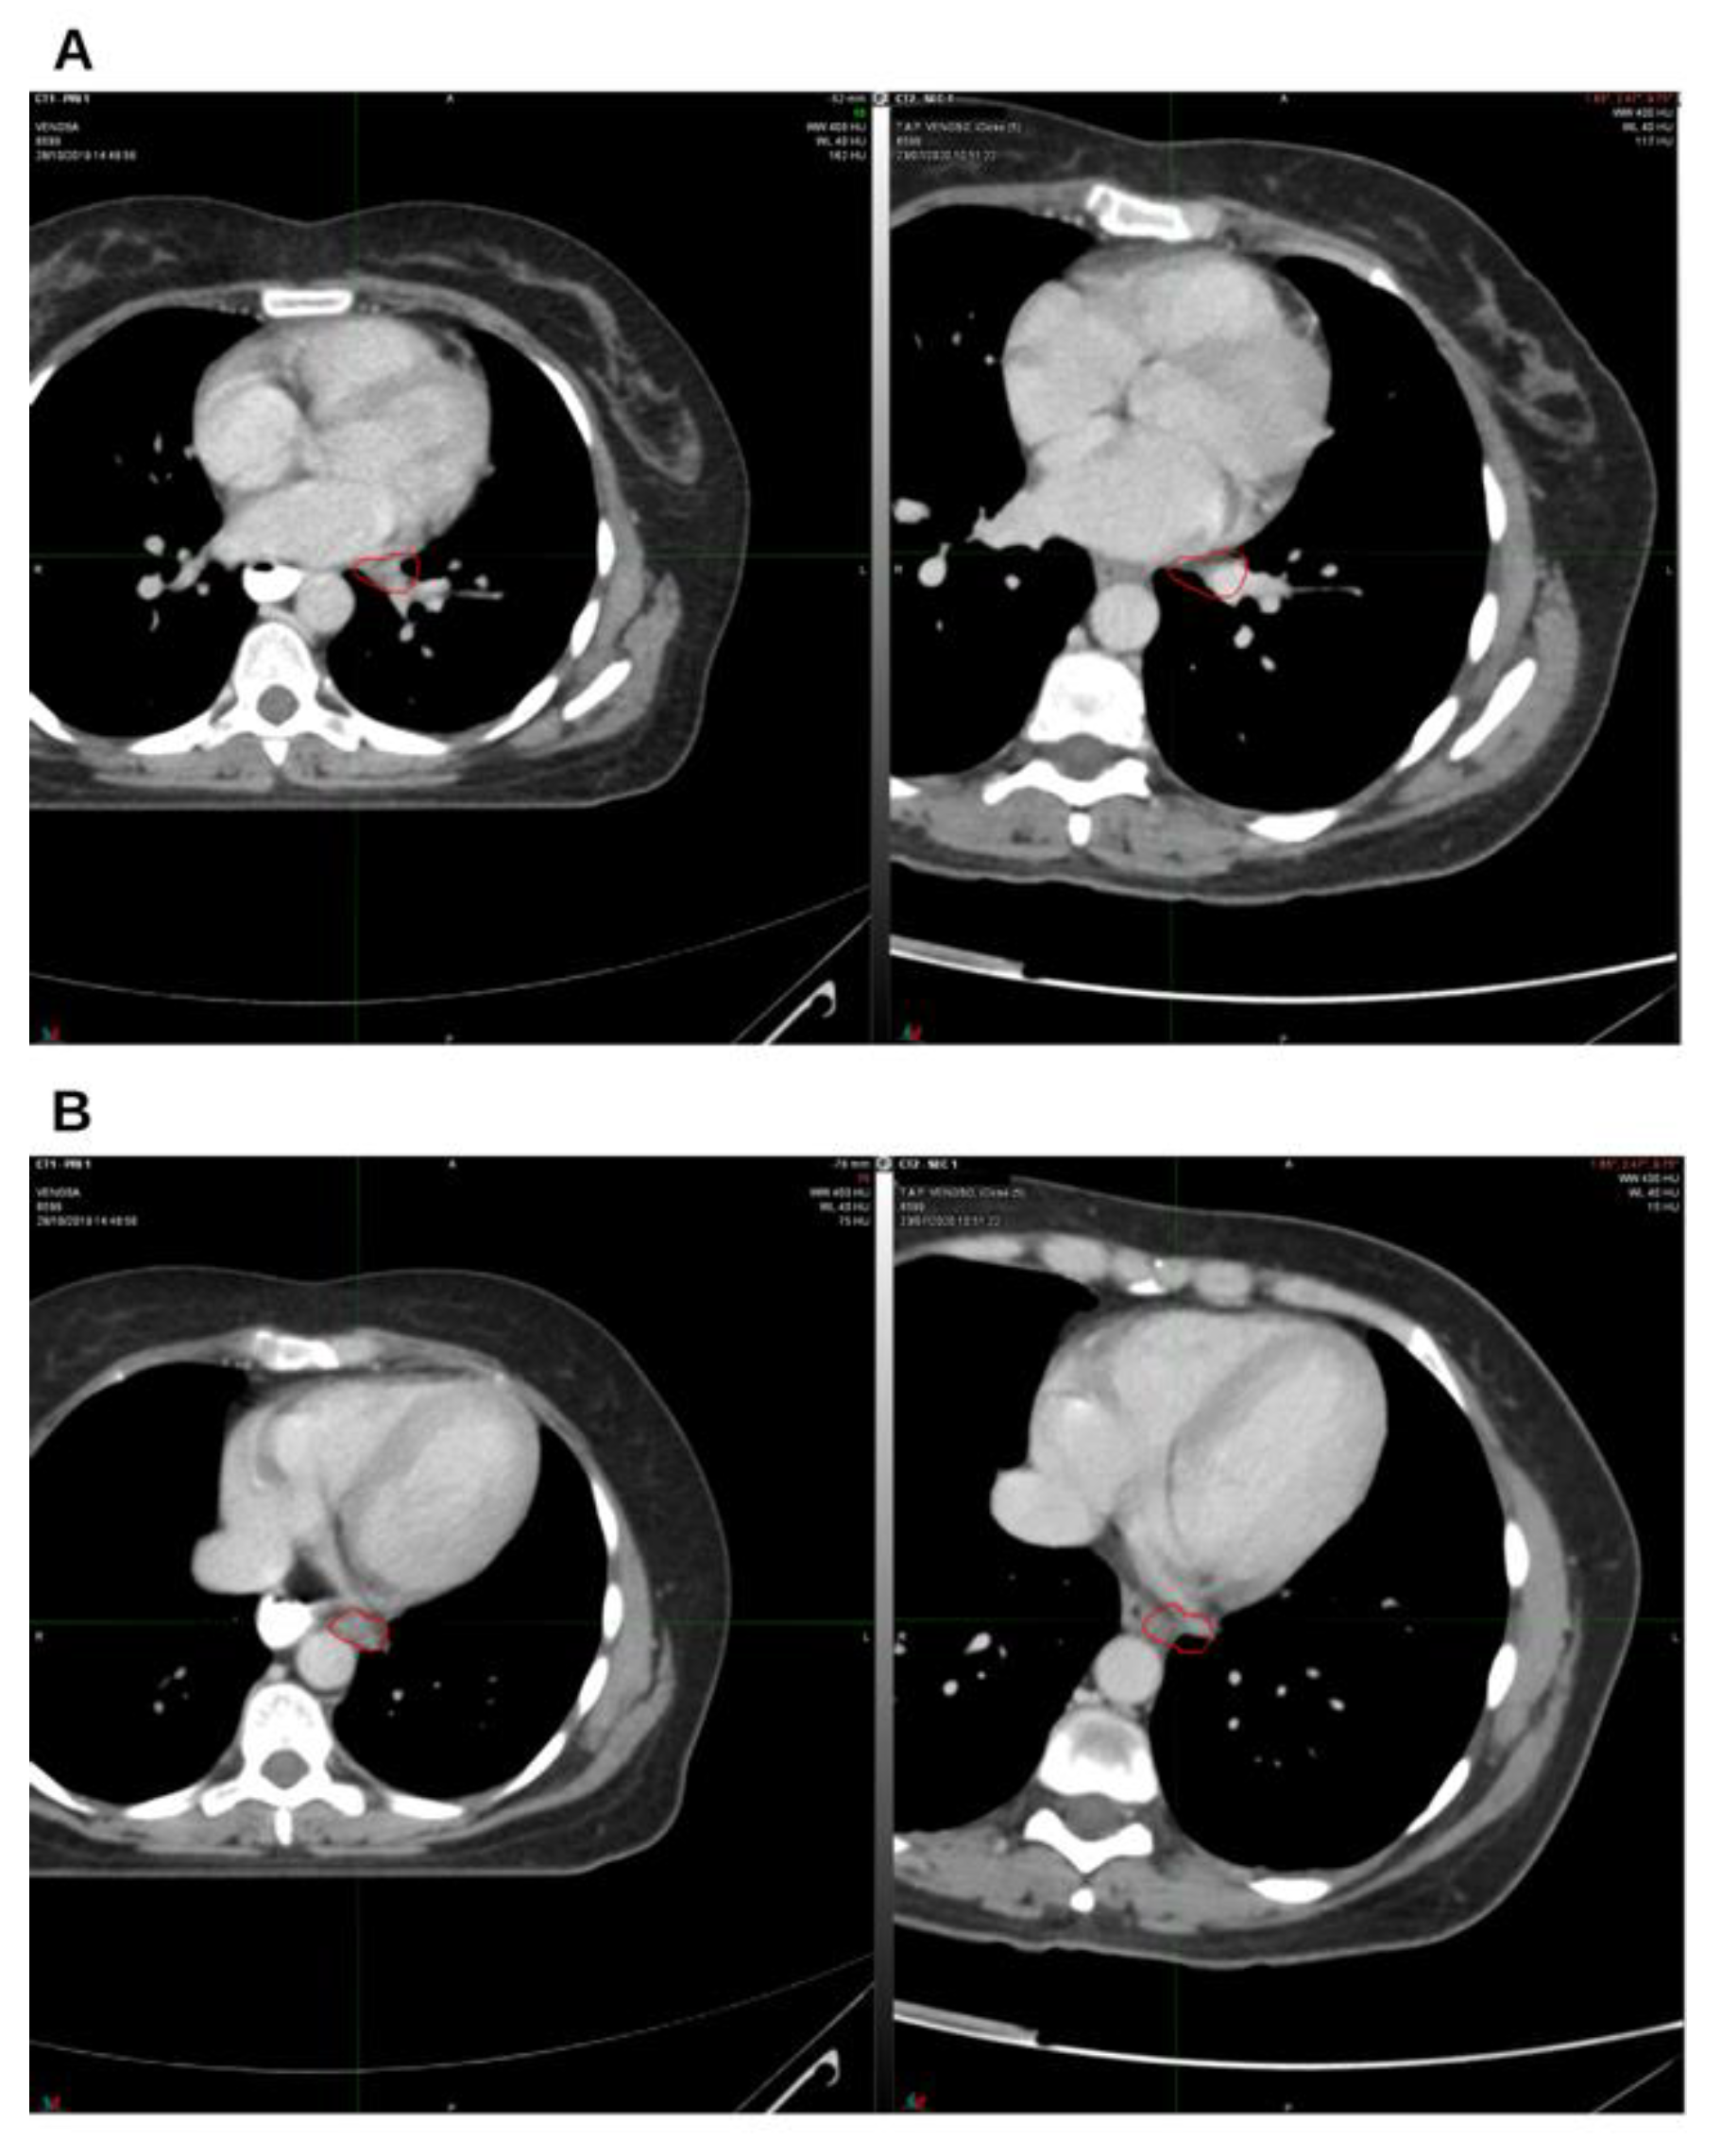

Background and Clinical Significance: Breast cancer is the most frequent malignancy in women. Advanced metastatic breast cancer is considered a treatable but incurable condition, with a median overall survival of only 2-3 years. Among its subtypes, triple-negative breast cancer (TNBC) accounts for a high proportion of breast cancer–related deaths. It is characterized by an aggressive clinical course, early recurrence, and a strong propensity for visceral and brain metastases. Case Presentation :We report the case of a Caucasian woman who, two years after being initially diagnosed and treated for TNBC, developed disease relapse with lung and mediastinal lymph node metastases. The patient received three months of chemotherapy combined with an adjuvant integrative protocol consisting of melatonin, cannabidiol, and oxygen–ozone therapy. This combined approach led to the complete disappearance of the lung nodules. Subsequently, stereotactic radiotherapy was performed and, in association with the ongoing integrative treatment, resulted in a significant reduction of mediastinal adenopathy. Introduction of immunotherapy, supported continuously by the same adjuvant strategy, achieved a complete and durable remission. Strikingly, the patient remained disease-free five years after the diagnosis of lung and mediastinal metastases. Conclusions: This clinical case highlights the potential benefit of using melatonin, cannabidiol, and oxygen–ozone therapy as part of an integrative approach in patients with aggressive metastatic TNBC. While it is not possible to establish causality from a single case, the sustained remission observed suggests that such unconventional adjuvant strategies could play a supportive role in enhancing the efficacy of standard oncologic therapies.